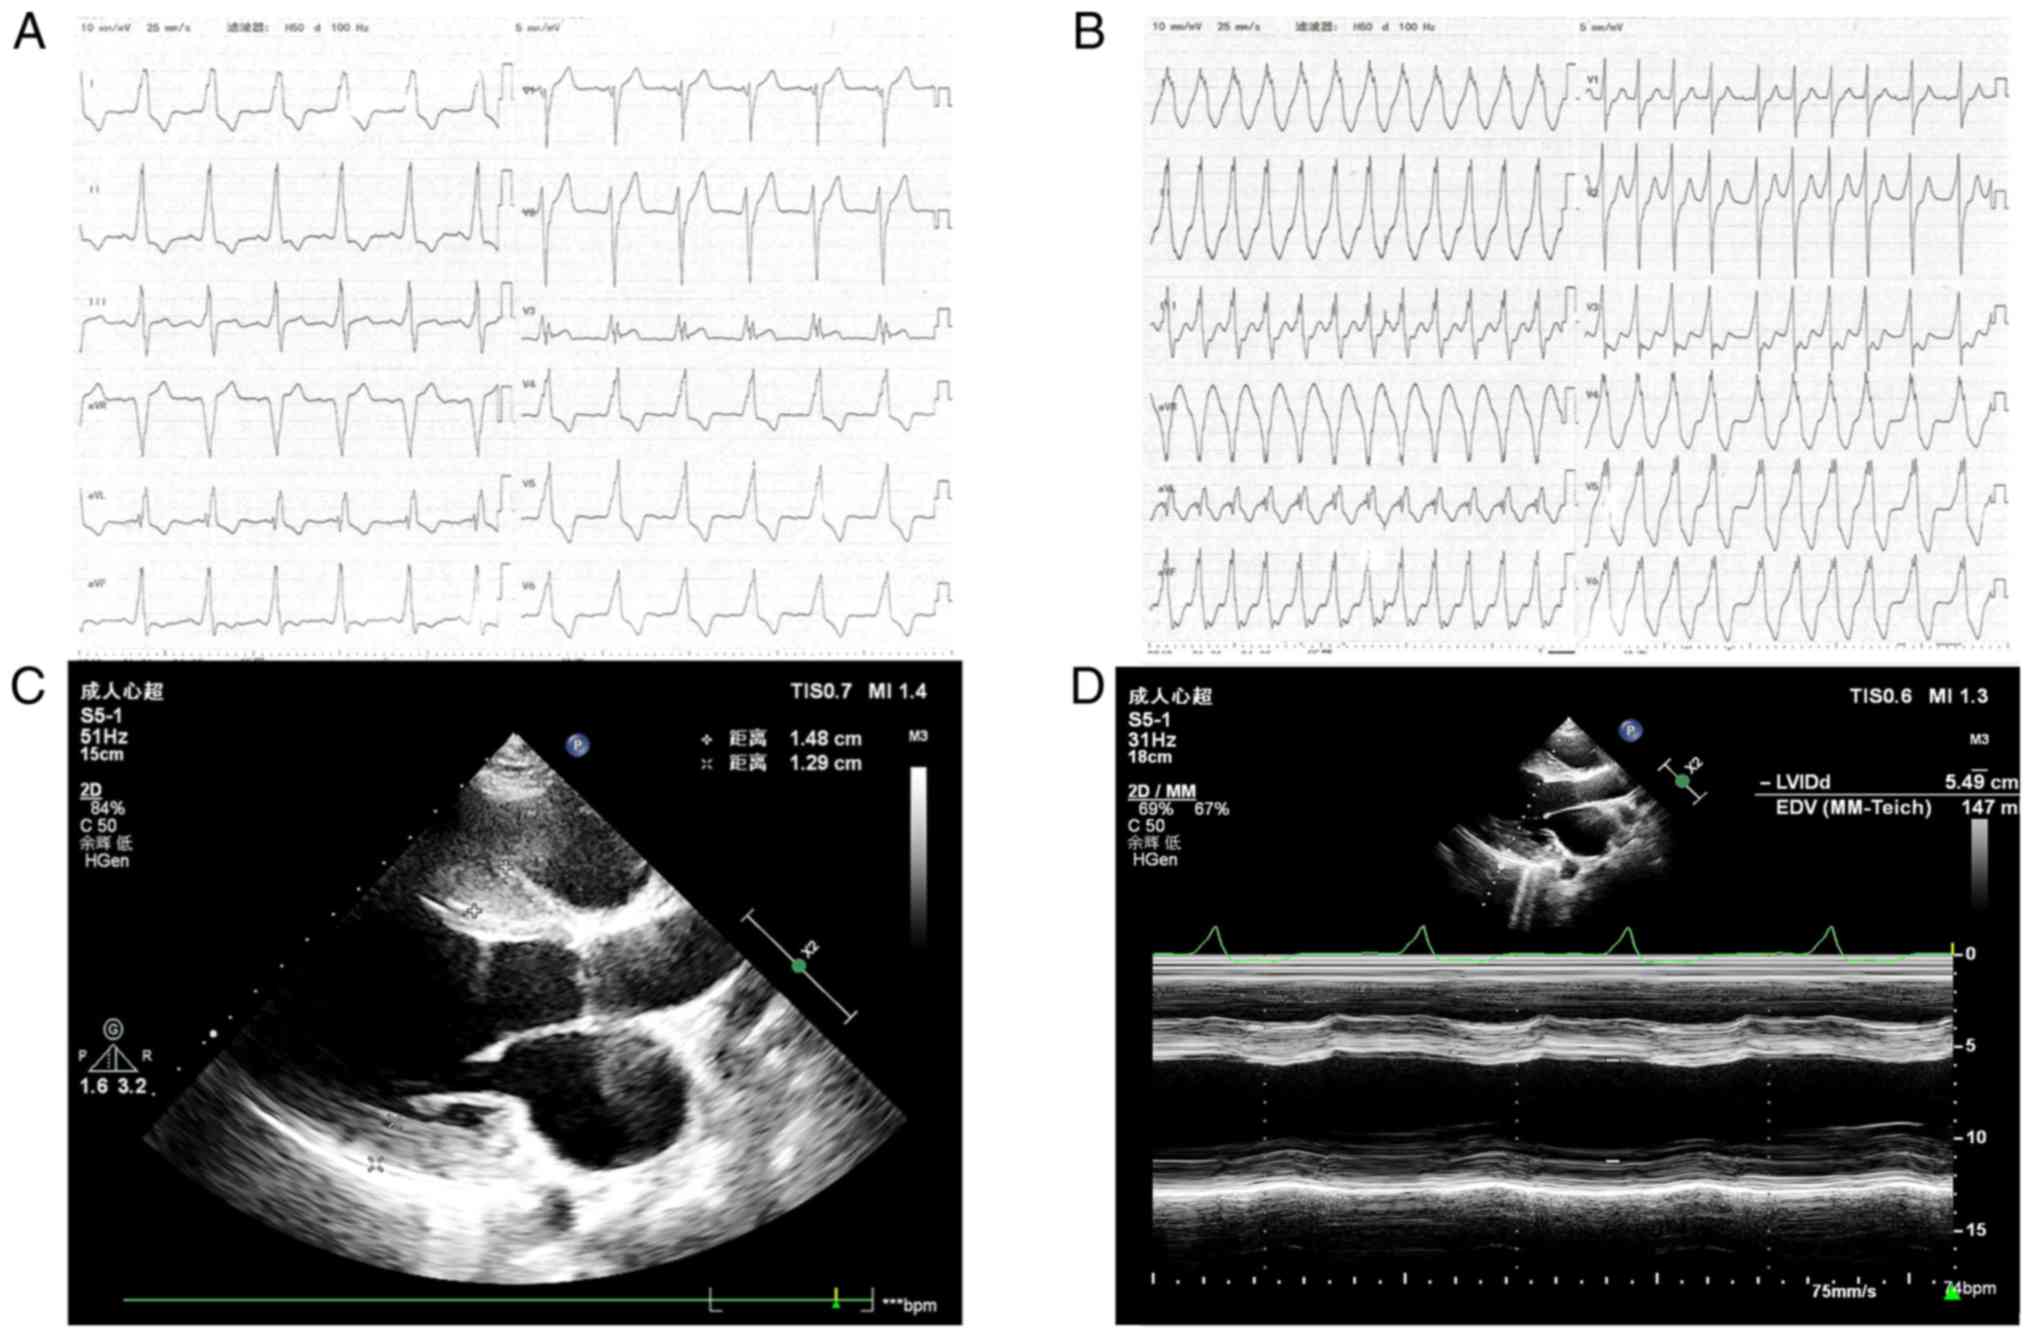

cardiomegaly. A ventricular pre-excitation pattern was evident in

the ECG (Fig. 4A). The ECG

examination revealed interventricular septum hypertrophy of 15 mm

and diffuse thickening of the left ventricular wall (Fig. 4C). The patient had a decreased left

ventricular systolic function with an ejection fraction of 37%

(Fig. 4D). Pathological diagnosis

Over one year, patient II.3 was admitted to the

hospital 3 times for heart failure decompensation, while pertinent

laboratory results and cardiac function estimated by ECG did not

indicate any significant alterations. The patient developed AF

(Fig. 4B) during his second

hospitalization and ~1 year later his sinus rhythm was restored

following catheter radiofrequency ablation. At the time of writing

of the manuscript, one year after the intervention, the patient

remained in a relatively stable state.